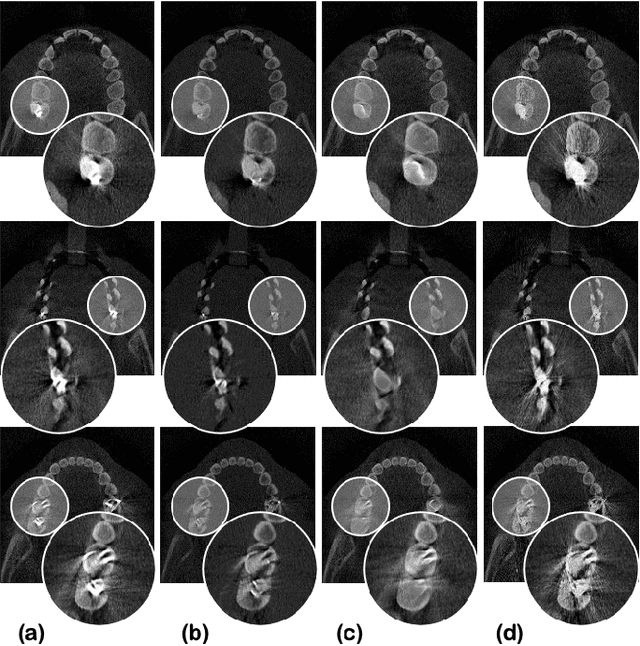

Abstract:Metal artifact reduction (MAR) is one of the most important research topics in computed tomography (CT). With the advance of deep learning technology for image reconstruction,various deep learning methods have been also suggested for metal artifact removal, among which supervised learning methods are most popular. However, matched non-metal and metal image pairs are difficult to obtain in real CT acquisition. Recently, a promising unsupervised learning for MAR was proposed using feature disentanglement, but the resulting network architecture is complication and difficult to handle large size clinical images. To address this, here we propose a much simpler and much effective unsupervised MAR method for CT. The proposed method is based on a novel beta-cycleGAN architecture derived from the optimal transport theory for appropriate feature space disentanglement. Another important contribution is to show that attention mechanism is the key element to effectively remove the metal artifacts. Specifically, by adding the convolutional block attention module (CBAM) layers with a proper disentanglement parameter, experimental results confirm that we can get more improved MAR that preserves the detailed texture of the original image.